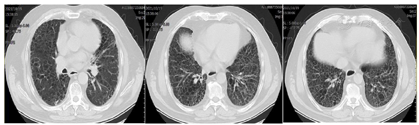

患者经治疗后肿瘤病灶明显缩小(图3,图4,图5,图6,图7,图8),定期于我院随访复查,目前一般情况良好,未见复发及远处转移。

PD-L1是一种跨膜糖蛋白,属于B7家族成员之一,一级结构包括290个氨基酸,亦由胞外区、疏水跨膜及尾部胞浆区组成[2]。有研究发现,PD-L1蛋白广泛表达于活化T淋巴细胞、巨噬细胞、B细胞等免疫细胞,还表达于多种类型的恶性肿瘤细胞表面,比如乳腺癌、胶质瘤、恶性黑色素瘤等[3]。PD-L1与其受体程序性死亡分子1 (PD-1)结合形成PD-1/PD-L1通路,该通路可介导形成机体的免疫抑制微环境,参与肿瘤细胞的免疫逃逸,继而促进肿瘤的发展。研究发现,27%~50%的肺癌患者可表达PD-L1[4,5],Koh等人[6]发现,在肺腺癌组织中PD-L1的阳性表达率为59%,且其阳性表达与患者淋巴结转移、组织分化程度及吸烟有关。有研究结果表明,肺鳞癌组织PD-L1阳性表达明显高于正常肺组织,PD-L1阳性表达与患者pTNM分期、淋巴转移有关,提示PD-L1在肺鳞癌的发生、进展过程中具有重要作用[3]。但目前单独研究PD-L1对肺鳞癌患者预后影响的报道甚少,尤其是伴有肺间质纤维化的肺鳞癌患者的相关研究更少,有待于大规模的临床试验。PD-L1抑制剂虽然可以达到预期的抗肿瘤效果,但这是一个非常复杂的过程,也有发生免疫相关不良事件的风险,包括诱发各种器官的炎症反应[7,8]。目前,其背后的机制仍不清楚,但先前的肺部疾病可能是免疫检查点抑制剂诱发肺炎的一个危险因素[9],所以由于肺炎的风险增加,肺间质纤维化合并肺癌患者接受免疫检查点抑制剂治疗的报道甚少。在以往的研究中,与传统非小细胞肺癌的化疗方案相比,抗PD-1治疗导致重度免疫相关性肺炎的发生率较高,但抗PD-L1治疗则不然[10]。也有研究显示,使用PD-1抑制剂患者3/4级免疫相关性肺炎的发生率仅略高于使用PD-L1抑制剂的患者[11]。此例病人为肺鳞状细胞癌伴肺间质纤维化,肿瘤细胞的PD-L1阳性表达百分比高达78%,因此在GP方案化疗的同时联合应用PD-L1抑制剂度伐利尤单抗,并在化疗与免疫联合治疗5疗程后以度伐利尤单抗单药维持。复查时可见右肺下叶的肿瘤病灶迅速且明显缩小,肺间质纤维化未见进展。患者治疗初期躯干部有散在皮疹出现,经抗过敏治疗后皮疹消失。患者1年半来复查病情稳定,未见复发及除淋巴结以外的其他部位转移,没有报告过除散在皮疹以外的免疫相关不良事件发生,也进一步证实了肺鳞癌病人化疗联合抗PD-L1药物作为一线治疗方案的可行性和安全性,为临床工作中肺鳞癌病人的治疗提供了新的思路。但目前病例数少,有待于大规模的临床试验。我们期望,在不远的未来,免疫治疗可使越来越多的肺癌患者获益。